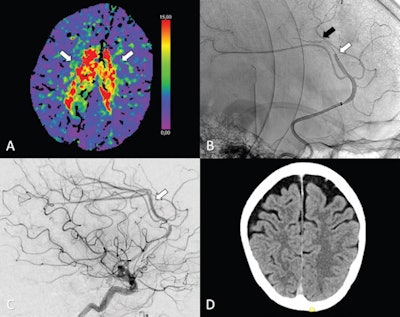

(A-C) Axial perfusion CT (time to maximum, > 6 seconds) at admission shows a bilateral deficit (arrows in A) in the territory of the anterior cerebral artery (ACA; i.e., azygos variant) because of a distal occlusion of the A3 segment (white arrow, sagittal view in B). Stent retriever thrombectomy (black arrow, sagittal view in B) was performed with full reperfusion shown on the final digital subtraction angiography image (arrow, sagittal view in C). (D) Follow-up at 24 hours shows no sign of infarction in the ACA on the axial contrast-unenhanced CT image. Image courtesy of Radiology.The researchers assessed early outcome, or outcomes within the first 24 hours after treatment, including any reports of bleeding in the brain and death.

The analysis showed that thrombectomy was a safe and technically feasible option. Within the first 24 hours after treatment, thrombectomy patients had similar outcomes to those who received best medical treatment alone, with or without intravenous thrombolysis. In addition, thrombectomy for primary isolated occlusions led to high rates of successful reperfusion in 76 of 94 patients (81%), according to the findings.